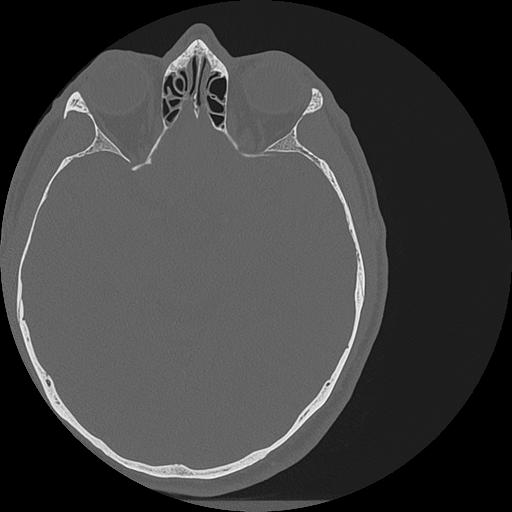

7 HUESO,,Vol,0.5,HUESO,,